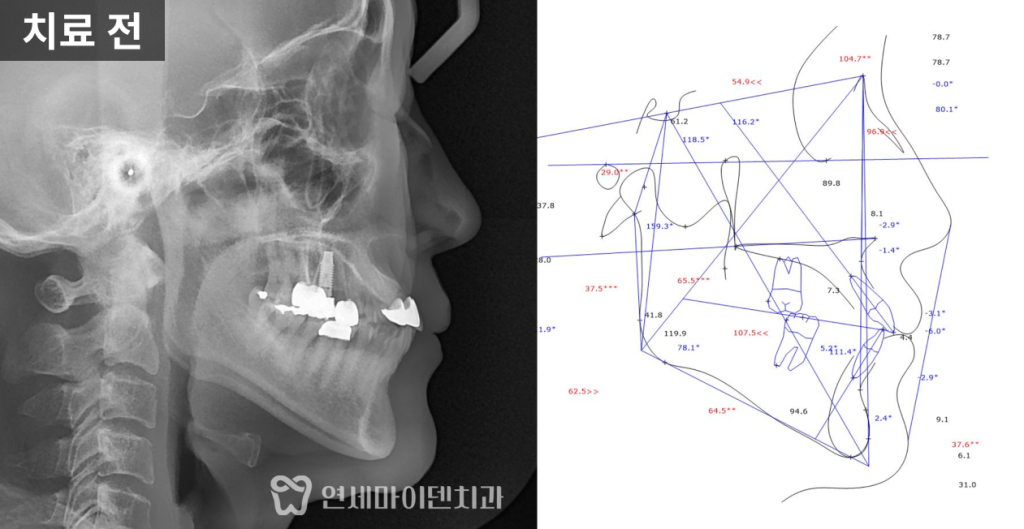

초기 진단에서 확인된 상태

중장년층 환자분들은 이미 과거에

보철 치료를 받아본 경험이 있는 경우가 많습니다.

이번 사례에서도 윗앞니 일부가

보철물로 연결되어 있었고,

아래 앞니는 배열이 고르지 못한 상태였습니다.

시간이 지나면서 기존 보철물의 심미성이 떨어졌고,

과거 교정 이후 다시 치아 사이에 틈이 생긴 점이

불편함으로 이어져 치료를 결정하게 되었습니다.

단순히 치아 배열만의 문제가 아니라,

기존 보철 상태와 현재의 교합 관계를

함께 살펴봐야 하는 상황이었습니다.

3급 부정교합의 특징과 잇몸 상태

검사 과정에서 치석이 많이 쌓여 있고,

잇몸이 전반적으로 부어 있으며

잇몸뼈가 내려간 소견이 확인되었습니다.

일부 치아 뿌리 끝에는

염증 소견도 동반되어 있었습니다.

방사선 사진에서는 윗턱보다 아래턱이

상대적으로 발달한 3급 부정교합(주걱턱) 이었고,

위턱 앞니는 앞으로 뻐드러진 상태였습니다.

이러한 골격적·치성적 특징은 치아 배열뿐 아니라

전체 교합 관계에도 영향을 주고 있었습니다.